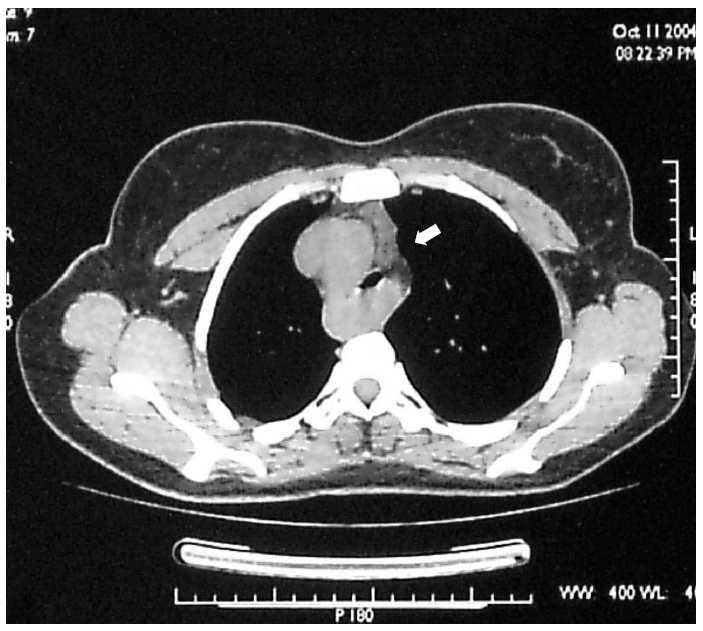

In view of the results we ordered a thorax CT-scan which showed a right aortic arch and an abnormal subclavia situation that compressed trachea and esofagus (fig. 2). This result was confirmed with a cateterisism.

Figure 2.--Thorax CT-scan.